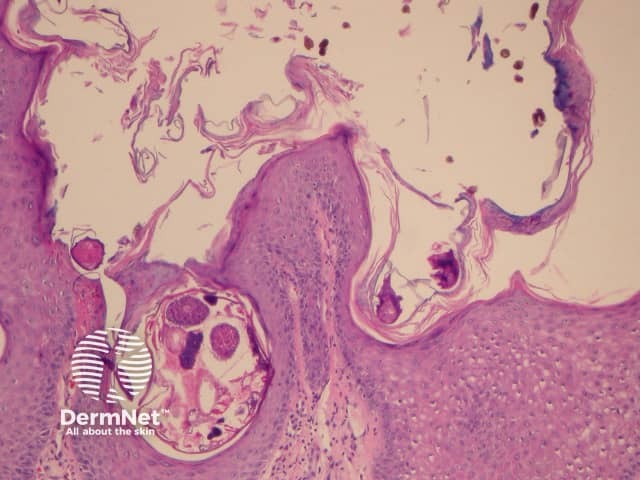

Scabies mites and eggs on palmar biopsy

Diagnosis is confirmed by identifying mites or eggs through microscopic examination of skin scrapings. In addition, diagnosis is also supported by evidence of hyperkeratosis.

Skin biopsy is rarely needed, but histology typically shows multiple mites within the thickened stratum corneum. The dermis shows infiltration by lymphocytes and eosinophils, with a higher ratio of CD8+ lymphocytes than normal.